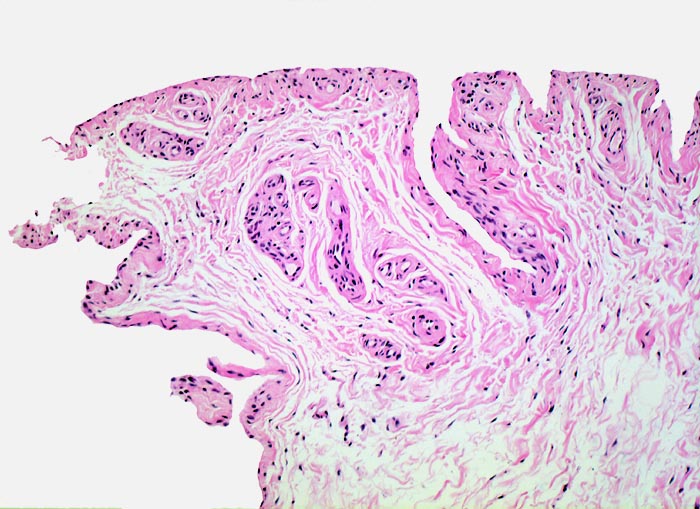

PathoPic – image database / PathoPic ID 5175 - normale Synovialis

normale Synovialis

Synovialis

Die Innenauskleidung von Gelenken, Sehnenscheiden und Bursen wird von einer spezialisierten epithelähnlichen Synovialmembran ausgekleidet. Diese sezerniert Synovia. Die Synovialis besteht aus 1-4 Synovialzellagen, die an der Unterseite mit einer Zone von lockerem gut vaskularisiertem kollagenem Bindegewebe verschmelzen, in dem Fettzellen, Fibroblasten, Mastzellen und Makrophagen vorkommen. Eine kontinuierliche Basalmembran ist nicht ausgebildet. Die Synovialzellen können flach und mesothelähnlich, spindelförmig, polyedrisch oder kubisch sein. Typ A Synoviozyten sind phagozytisch tätig, Typ B Zellen produzieren reichlich Proteine und haben entsprechend ein gut entwickeltes rauhes endoplasmatisches Reticulum.

Synovialis von Fingergelenk

100